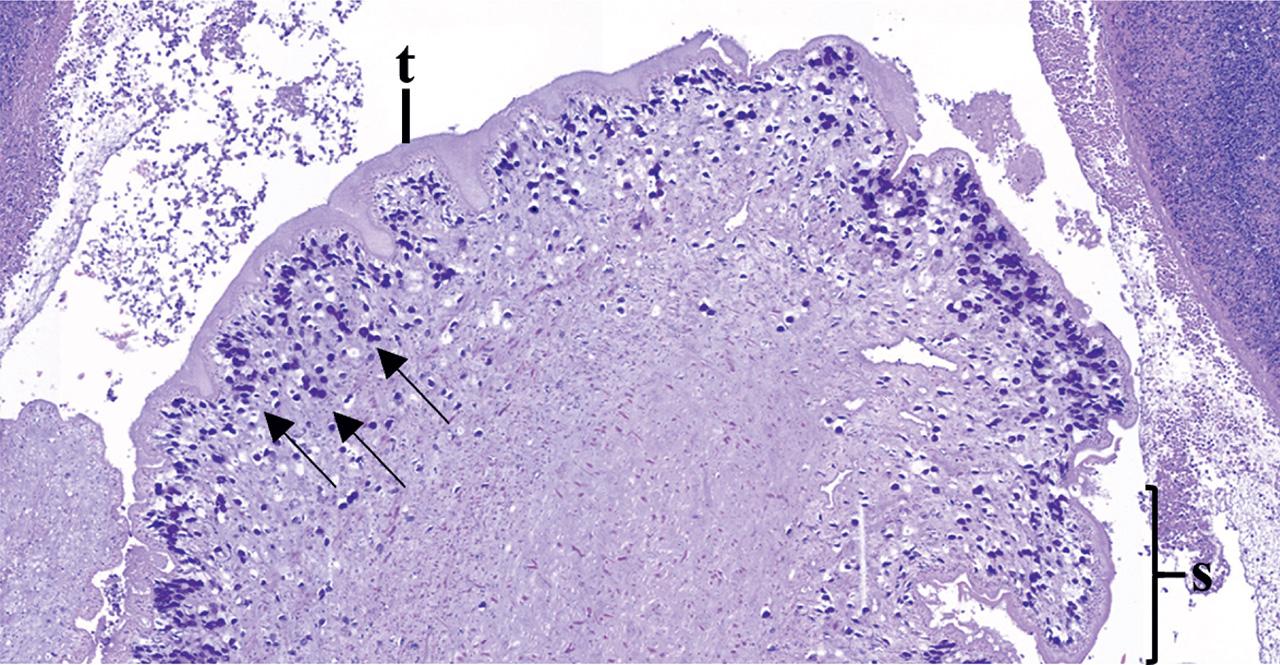

At the histopathology exam, multiple pyogranulomas were found in the liver, with a core of viable and degenerate neutrophils, all rounded with multiple layers of macrophages, lymphocytes, plasma cells, eosinophils, and a thick capsule of fibrous connective tissue. In the center, the presence of an approximately 1 cm long metacestode was noted (Fig. 1). The larva was moderately decomposed, but the presence of tegument, a loose mesenchymal parenchyma and calcareous corpuscles were still recognizable (Fig. 2). No scolices were observed. The adjacent hepatic parenchyma was unremarkable.

Histologic details of the metacestode parasitic structure included in the cyst, with absence of a digestive tract, tegument (t), segmented body (s) and the presence of calcareous corpuscles (arrows). Hematoxylin and eosin, 6X.